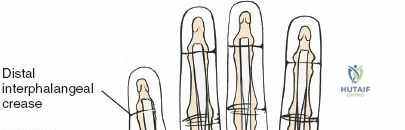

Landmarks and Incision

Surface landmarks guide the incision. In the digits, these include the distal phalangeal crease (just proximal to the distal interphalangeal joint), the proximal interphalangeal crease, and the metacarpophalangeal crease. In the palm, the distal palmar crease and thenar/hypothenar creases are important.

The skin incision must provide adequate exposure without creating straight lines across joint creases, which can lead to scar contracture. The Bruner zigzag incision is the standard for digital access due to its excellent exposure and prevention of flexion contractures. It incorporates the natural creases and extends proximally and distally in a zigzag fashion along the length of the digit. The apices of the V's are typically located over the mobile skin of the phalanges, avoiding the fixed skin over the joint creases.

- Finger Incision (Bruner): Begins dorsally/mid-laterally over the distal phalanx, angles volarly, crosses the volar skin crease, then angles back to the mid-lateral line, avoiding straight lines across joints. This allows creation of triangular skin flaps.